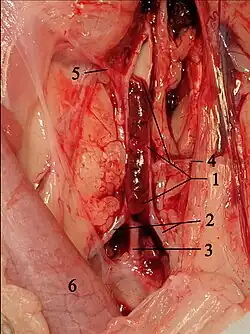

In cats, the blood clots originate mainly in the left atrial auricle.[8] They or parts of them are carried along with the blood flow, enter the aorta via the left ventricle, get stuck at vascular outlets and block them. This condition is called thromboembolism. In cats, this occurs predominantly in the aorta in the area of its terminal branch, i.e., at the outlet of the two external iliac arteries (Aa. iliacae externae). This is also called "saddle thrombus" or "riding thrombus". This results in an ischemia to the rear extremities. In addition, platelets release thromboxane and serotonin, which leads to vasoconstriction and thus to reduced blood flow even to blood vessels that are not directly affected. Serotonin also stimulates nociceptor, which contributes to the high painfulness of the disease.[9] Only in 10% of cases are other blood vessels affected, for example the brachial artery, pulmonary arteries, cerebral circulation, intestinal vessels or coronary arteries.[10][11]

The obvious treatment, reopening of the vessel by drug dissolution (thrombolysis) or invasive removal of the clot (thrombectomy), as long established in human medicine for occlusive diseases such as cerebral infarction or myocardial infarction, provides unsatisfactory results in cats and is therefore no longer recommended.[32] Thrombolysis with streptokinase, urokinase or tissue-type plasminogen activator has not improved treatment success in various studies. This usually results in frequently fatal reperfusion injury, hyperkalemia, metabolic acidosis, kidney failure, and bleeding, so that the survival rate is often lower than with conservative treatment.[47][48] In human medicine, such treatments are only performed in highly specialized facilities (cardiac centers, stroke units) with a high level of personnel and equipment. Surgical removal of the thrombus is also rarely performed in veterinary medicine because of the associated risks, although it can be successful in individual cases.[49] It is associated with the same complications as thrombolysis and is therefore no longer recommended. Therefore, the current focus is on endogenous dissolution of the clot and thus spontaneous revascularization, which occurs quickly enough in just under 40% of cases.[47]